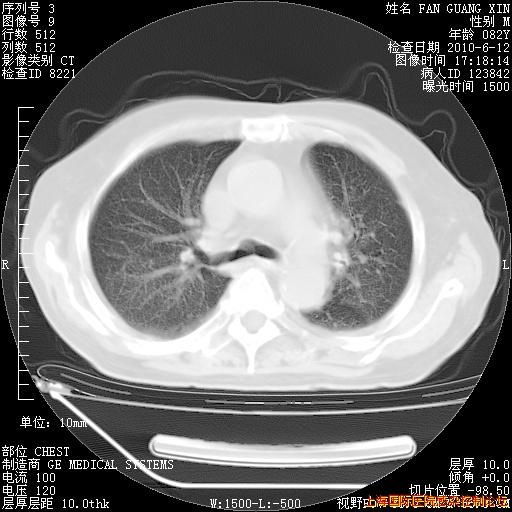

6月12日纵膈窗